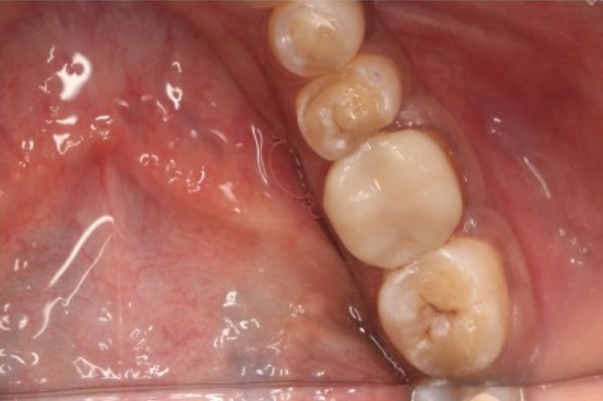

On the other hand, Onlays cover the edge of the tooth that has been affected by damage or decay to the cusp of your tooth.

This is an efficient dental procedure and can last up to 10-15 years. It is a conservative filling near the edges of teeth and lasts for years if maintained properly… They may pop out once in a while and can be re-attached by the dentist.